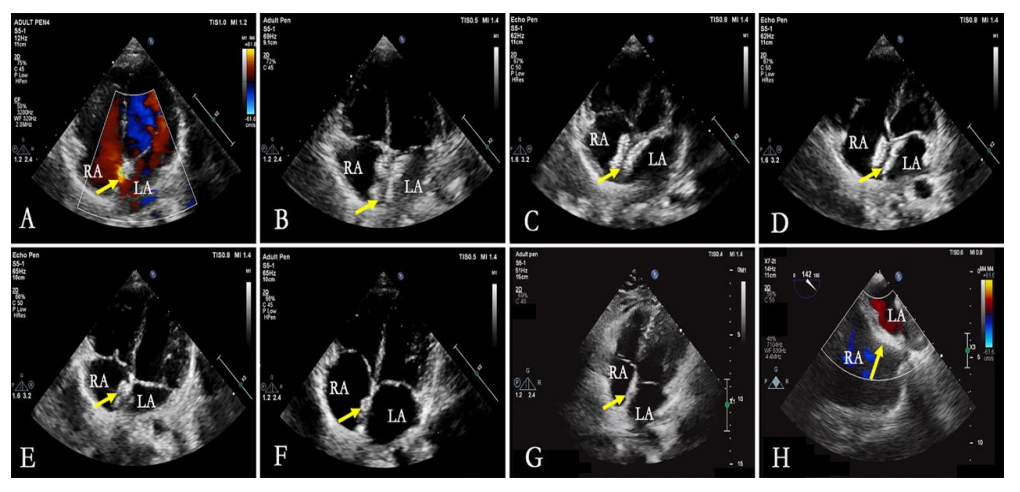

e图7. 生物可降解封堵器24个月随访期间形态变化的超声心动图评估(RA-右心房,LA-左心房)

A. 术前评估显示房间隔缺损(箭头指示)

B-G. 分别为出院前及术后1、3、6、12、24个月时的经胸超声心动图四腔心切面,显示封堵器形态(箭头指示)

H. 24个月时经食道超声心动图显示封堵器降解后房间隔形态(箭头指示)